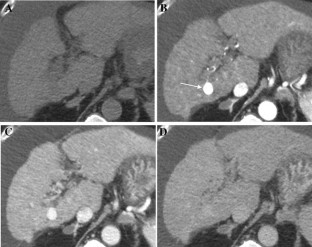

Fig. 3